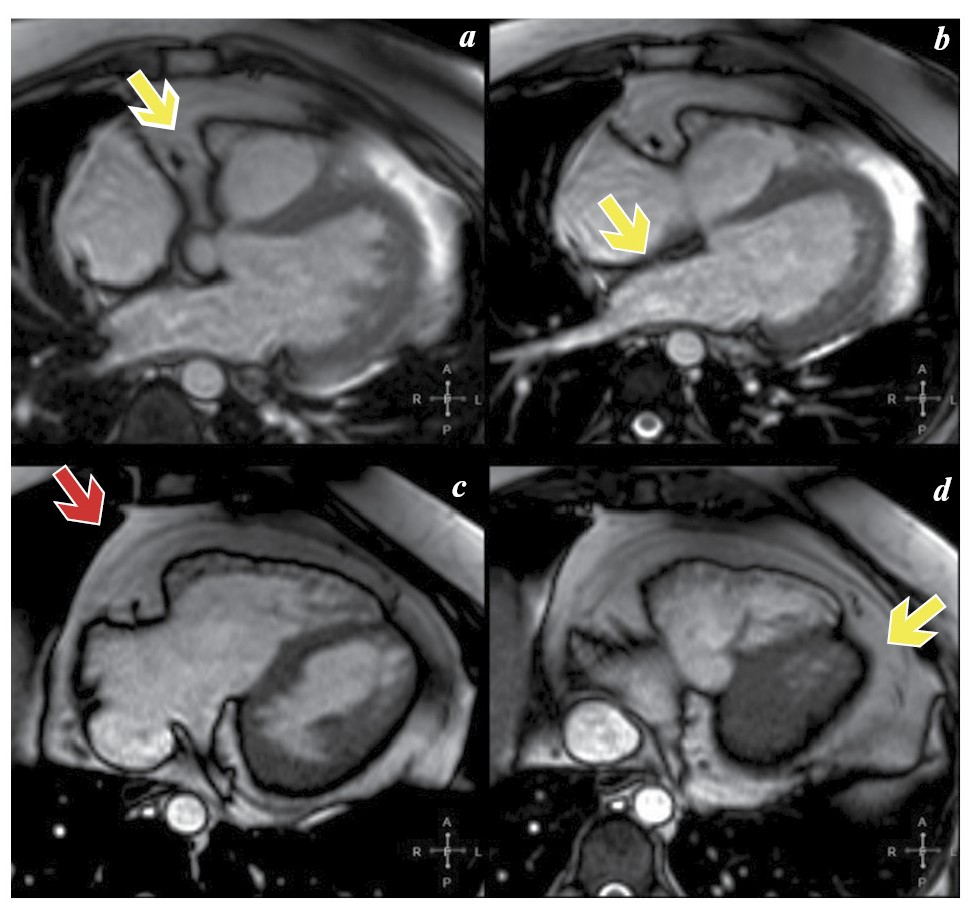

По данным трансторакальной ЭхоКГ: размеры полостей сердца в пределах нормальных значений (КДР ЛЖ – 4,9 см, КСР ЛЖ – 3,6 см, ЛП – 3,6 см, индекс объема ЛП – 21 мл/м2, переднезадний размер ПЖ – 2,7 см, площадь правого предсердия – 17 см2), небольшое снижение глобальной сократимости ЛЖ (ФВ≈45%). Отмечалась сепарация листков перикарда по всему периметру сердца, преимущественно в области атриовентрикулярных борозд (до 1,6 см справа, до 1,2 см слева) со следовым количеством свободной жидкости и наличием дополнительных масс, по структуре напоминающих жировую ткань (рис. 2, a, b, указано стрелкой). Признаков экссудативного и констриктивного перикардита не выявлено, однако требовалось проведение дифференциального диагноза между жировой тканью и фибриновым выпотом.

Рис. 2. ЭхоКГ (жировое отложение указано стрелкой).

Fig. 2. Echocardiography (fat deposition is indicated by an arrow).